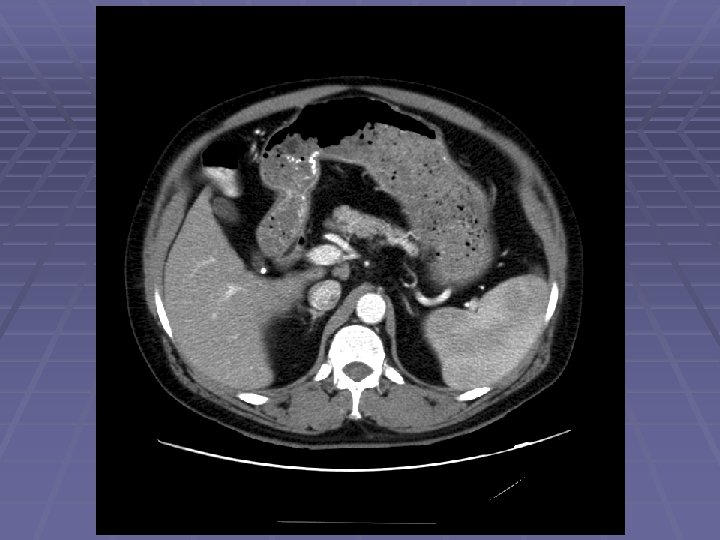

Pancreatic Mass at CT